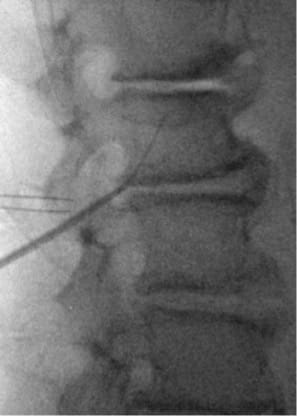

- In PA view, introduce guide needle just off midline from the superior L4 SP border towards the ipsilateral L3 TP–SAP junction marker; in lateral view, advance anteriorly to TP to traverse L2–L3 intertransversarii (~45°).

- In the lateral view, advance the guidewire towards the inferior dorsal L2 body; adjust depth if resistance is encountered. Prior to removing the guide needle and exchanging for the introducer sheath/dilator, use a #11 scalpel to make a stab incision along the guide needle trajectory adjacent to the L4 SP to create room for the introducer sheath/dilator.

- Insert lead anterior to TP; retract introducer sheath to deploy lead and confirm tine engagement around intertransversarii via push–pull test under low-dose live fluoroscopy in lateral and AP view.